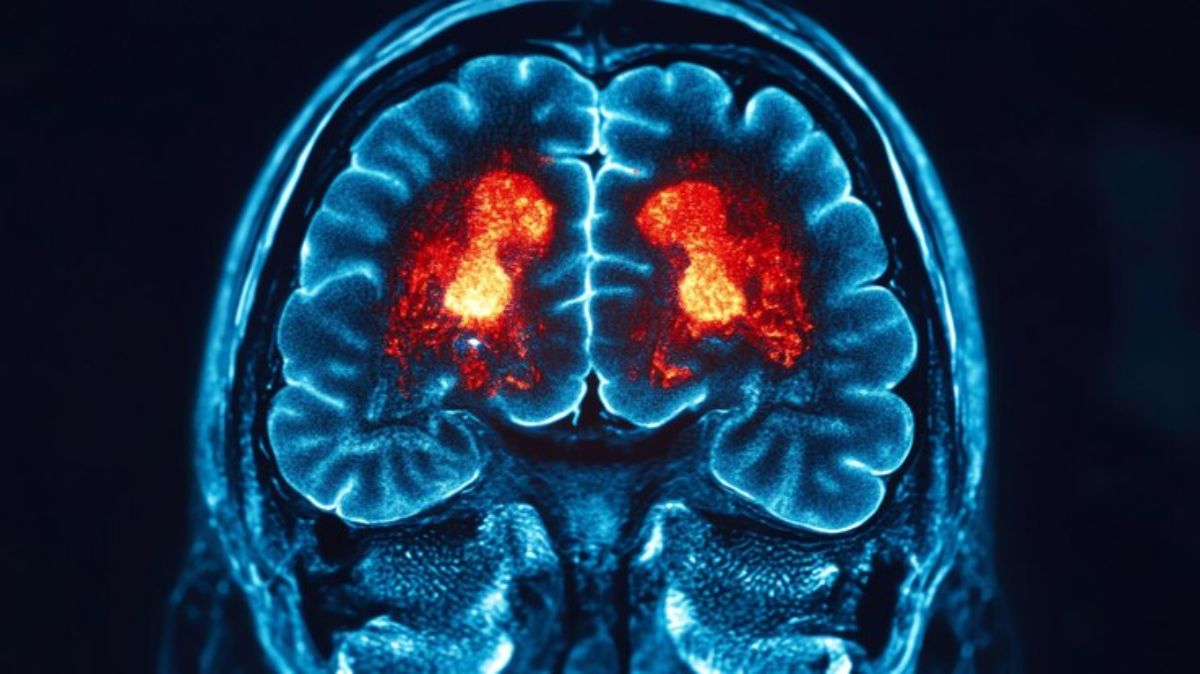

மூளைக் கட்டி என்பது ஒரு ஆபத்தான நோயாகும், இது பல காரணங்களால் ஏற்படலாம். இந்தக் காரணங்கள் கட்டியின் வளர்ச்சிக்கு பங்களிக்கின்றன, ஆனால் அதே நேரத்தில் பெரும்பாலான சந்தர்ப்பங்களில் அவை மூளைக் கட்டிக்கு நேரடி காரணம் அல்ல என்பதைப் புரிந்துகொள்வதும் முக்கியம். அத்தகைய சூழ்நிலையில், இந்தக் காரணங்களைப் புரிந்துகொண்டு மருத்துவரிடம் அவற்றைப் பற்றிப் பேசுவதன் மூலம், சரியான நேரத்தில் சிகிச்சைக்கான முடிவை எடுக்க முடியும். மூளைக் கட்டியைத் தடுக்க வாழ்க்கை முறை மற்றும் உணவில் ஏற்படும் மாற்றங்களை விட விழிப்புணர்வு மிக முக்கியமானது.

மூளைக் கட்டிகளுக்கான ஆபத்து காரணிகளைப் புரிந்துகொள்வது சாதாரண மக்களும் மருத்துவர்களும் இருவருக்கும் முக்கியம். மூளைக் கட்டிகளுக்கான காரணங்கள் சரியாகத் தெரியவில்லை என்றாலும், சில காரணிகள் ஆபத்தை அதிகரிக்கின்றன. இந்தக் காரணிகள் குறித்த விழிப்புணர்வை அதிகரிப்பதன் மூலம், ஆபத்தை ஓரளவு குறைக்கலாம்.